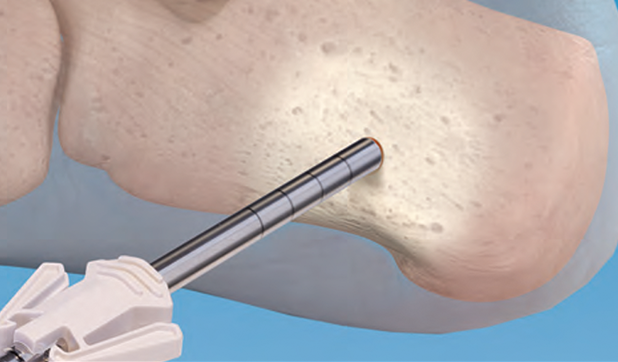

Ein kabelloses, komfortables System für kleine Knochen. Die leistungsstarke Lithium-Ionen-Technologie sorgt für die nötige Leistung, während die praktische Sterilisation in einem Schritt den Bedienkomfort erhöht.